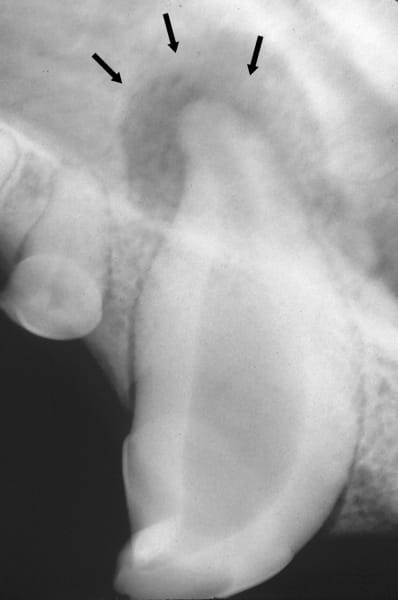

The problem tends to get worse with age as plaque turns to tartar tartar causes gum recession teeth become loose and some are damaged or fall out. Whether its a tooth fracture or decay it would be very painful if your dogs loose tooth fell out on its own or if you. Chewing on something a walnut and then the tooths root damaged its anchor in the gum in turn. Bannon says and pulling a tooth can break a root leaving part behind and leading to an infection. Tooth Luxation or Avulsion in Dogs.

It will involve general anesthesia and will be fairly expensive but the results may amaze you. Tooth luxation is the clinical term for a dislocation of the tooth from its normal spot in the mouth. Broken teeth that dont fall out on their own either need to be. These teeth look kind of nasty though. One loose lost or rotting tooth caused by bad dental hygiene is unlikely to be a standalone issue and removal of loose teeth and a thorough dental clean-up can help your dog to keep their.